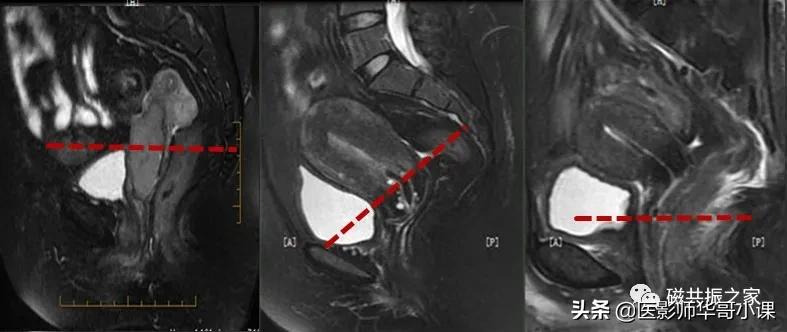

在横轴位和冠状位上定位。在横轴位上找到显示子宫体最大的层面,使定位线垂直于当前子宫内膜长轴,在冠状位上调整角度使定位线平行于子宫全长长轴(平行于子宫颈和子宫底中点的连线);如是宫颈病变,应以宫颈管为基准定位。左右扫描范围包括整个子宫,需包括整个病变范围。

在冠状位和矢状位上定位,在矢状位上找到显示子宫全景最好的层面,如需了解宫颈病变,使定位线垂直于宫颈管长轴(图A),如需了解子宫内膜病变,使定位线垂直于子宫内膜长轴(图B)。在冠状位调整角度使两侧对称扫描,扫描范围上至子宫上缘下至耻骨联合,需包括整个病变范围,如视察转移性病变需加大扫描范围。